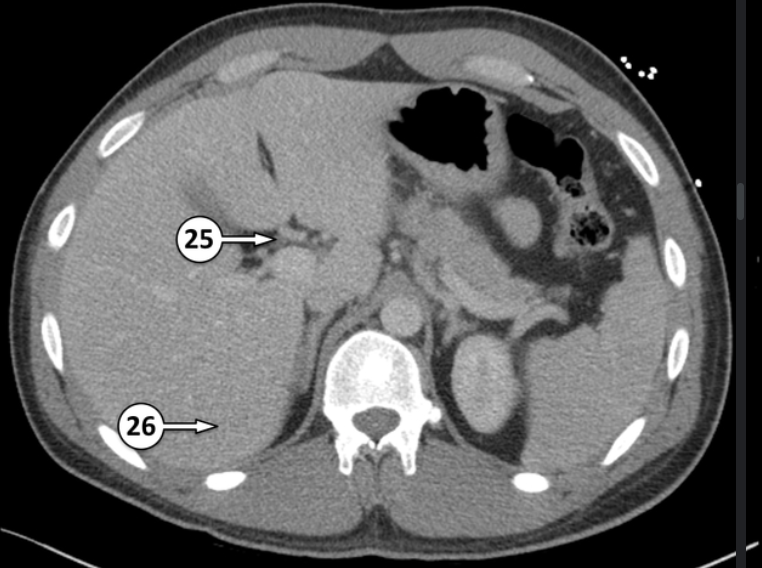

Label 25 and 26

Common hepatic duct

Segment VI of the liver